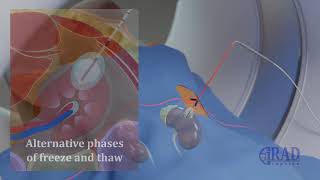

Samsung Medical Center_Image-guided Tumor Ablation Training (SITAT) What is a Tumor Ablation?

What is a Tumor Ablation? Renal Tumor Ablation (CT guided Cryoablation of kidney Tumor)

Samsung Medical Center_Image-guided Tumor Ablation Training (SITAT) What is a Tumor Ablation?

What is a Tumor Ablation? Renal Tumor Ablation (CT guided Cryoablation of kidney Tumor)